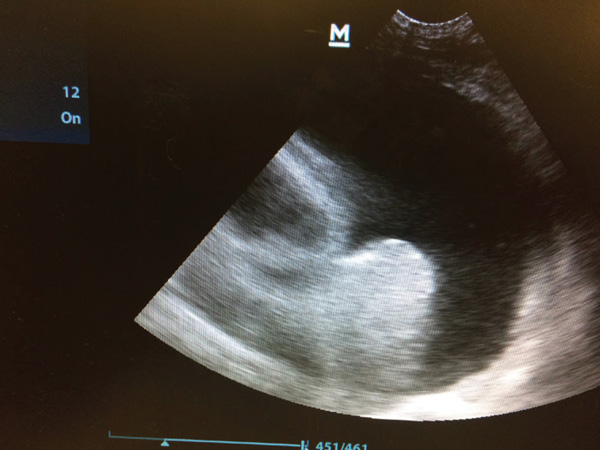

Point-of-care ultrasound is a tool to be used alongside the physical examination in the initial assessment of the dyspnoeic patient. No clipping is required, instead parting the fur and application of spirit to the skin should provide adequate contact for the probe. Placement of the probe in the rib spaces at numerous places dorsally and ventrally in numerous sites on both the left and right hemithorax will allow for assessment of pleural space disease and pulmonary disease. Pleural effusion and pericardial effusions can be identified easily as largely anechoic areas (Figure 3a). However, exudates may appear to be more echogenic. Ultrasound features of lung disease include the presence of ‘B lines’ or 'comet tails’ obliterating the normal ultrasound-gas interference (Figures 3b and 3c) With practice, cardiac chambers and the presence of a ‘glide sign’ can also be assessed on point-of-care ultrasound. Placement of the probe vertically between the ribs on the right hemithorax over the apex heartbeat allows visualisation for the four chamber view and then, with movement of the probe horizontally and cranially, the left atria to aorta ratio can be assessed. This requires practice and care should be taken to ensure correct chambers are identified before attempting a measurement. Increased left atria to aorta ratio suggests cardiac disease as strongly as the case of dyspnoea (Figure 4). A glide sign or ‘sliding lung’ represents the pleural-pulmonary line and in the absence of pleural space disease the lung glides along the thoracic wall as the patient breathes in and out. Absence of this line is suggestive of a pneumothorax.

Figure 3a. Pleural effusion

Figure 4. Enlarged left atrium to aorta